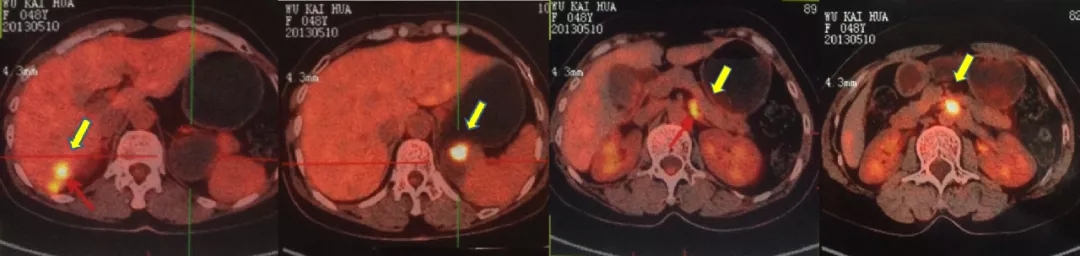

2016.10.14查PET-CT: 盆腔内软组织密度灶,FDG代谢异常增高,考虑转移灶;右肝后下段包膜处结节样、片状转移灶;左肾前方斑片状,腹主动脉管壁处(L3椎体水平)FDG代谢轻度增高,考虑肿瘤活性组织存在。

PET-CT检查结果